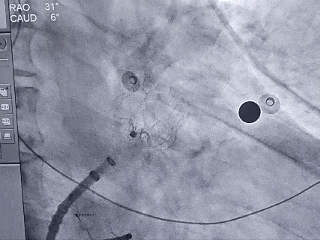

释放LAFDQ-26封堵器

封堵器展开后造影

牵拉试验:封堵器拉出心耳

封堵器牵拉未回弹

牵拉后造影,封堵器移位

上缘未挂住梳状肌,下缘露肩,导致牵拉不稳定,全回收封堵器并更换使用LAFDQ-29封堵器。